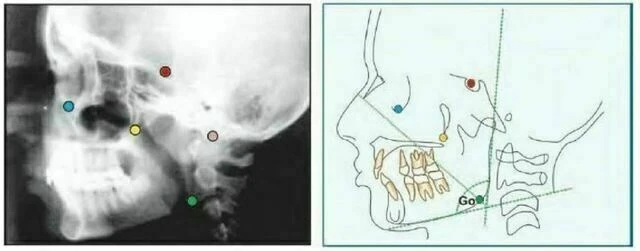

Orbitale (Or) là điểm nằm ở vị trí thấp nhất trên xương ổ mắt. Trên phim cephalogram theo chiều trước sau, mỗi điểm nằm riêng biệt nhau nhưng trên phim cephalogram mặt bên thì đường viền xương ổ mắt trùng nhau. Thông thường, điểm thấp nhất trên đường trung bình của xương ổ mắt được dùng để xác định mặt phẳng Frankfort.

Gonion (Go) là điểm nằm ở vị trí sau nhất và thấp nhất ở góc xương hàm dưới. Nó có thể được xác định bằng cách xem xét thông thường hoặc bằng cách chia đôi góc tạo bởi đường giao nhau của cành đứng và cành ngang xương hàm dưới, cho đường phân giác góc này cắt đường viền xương hàm dưới.